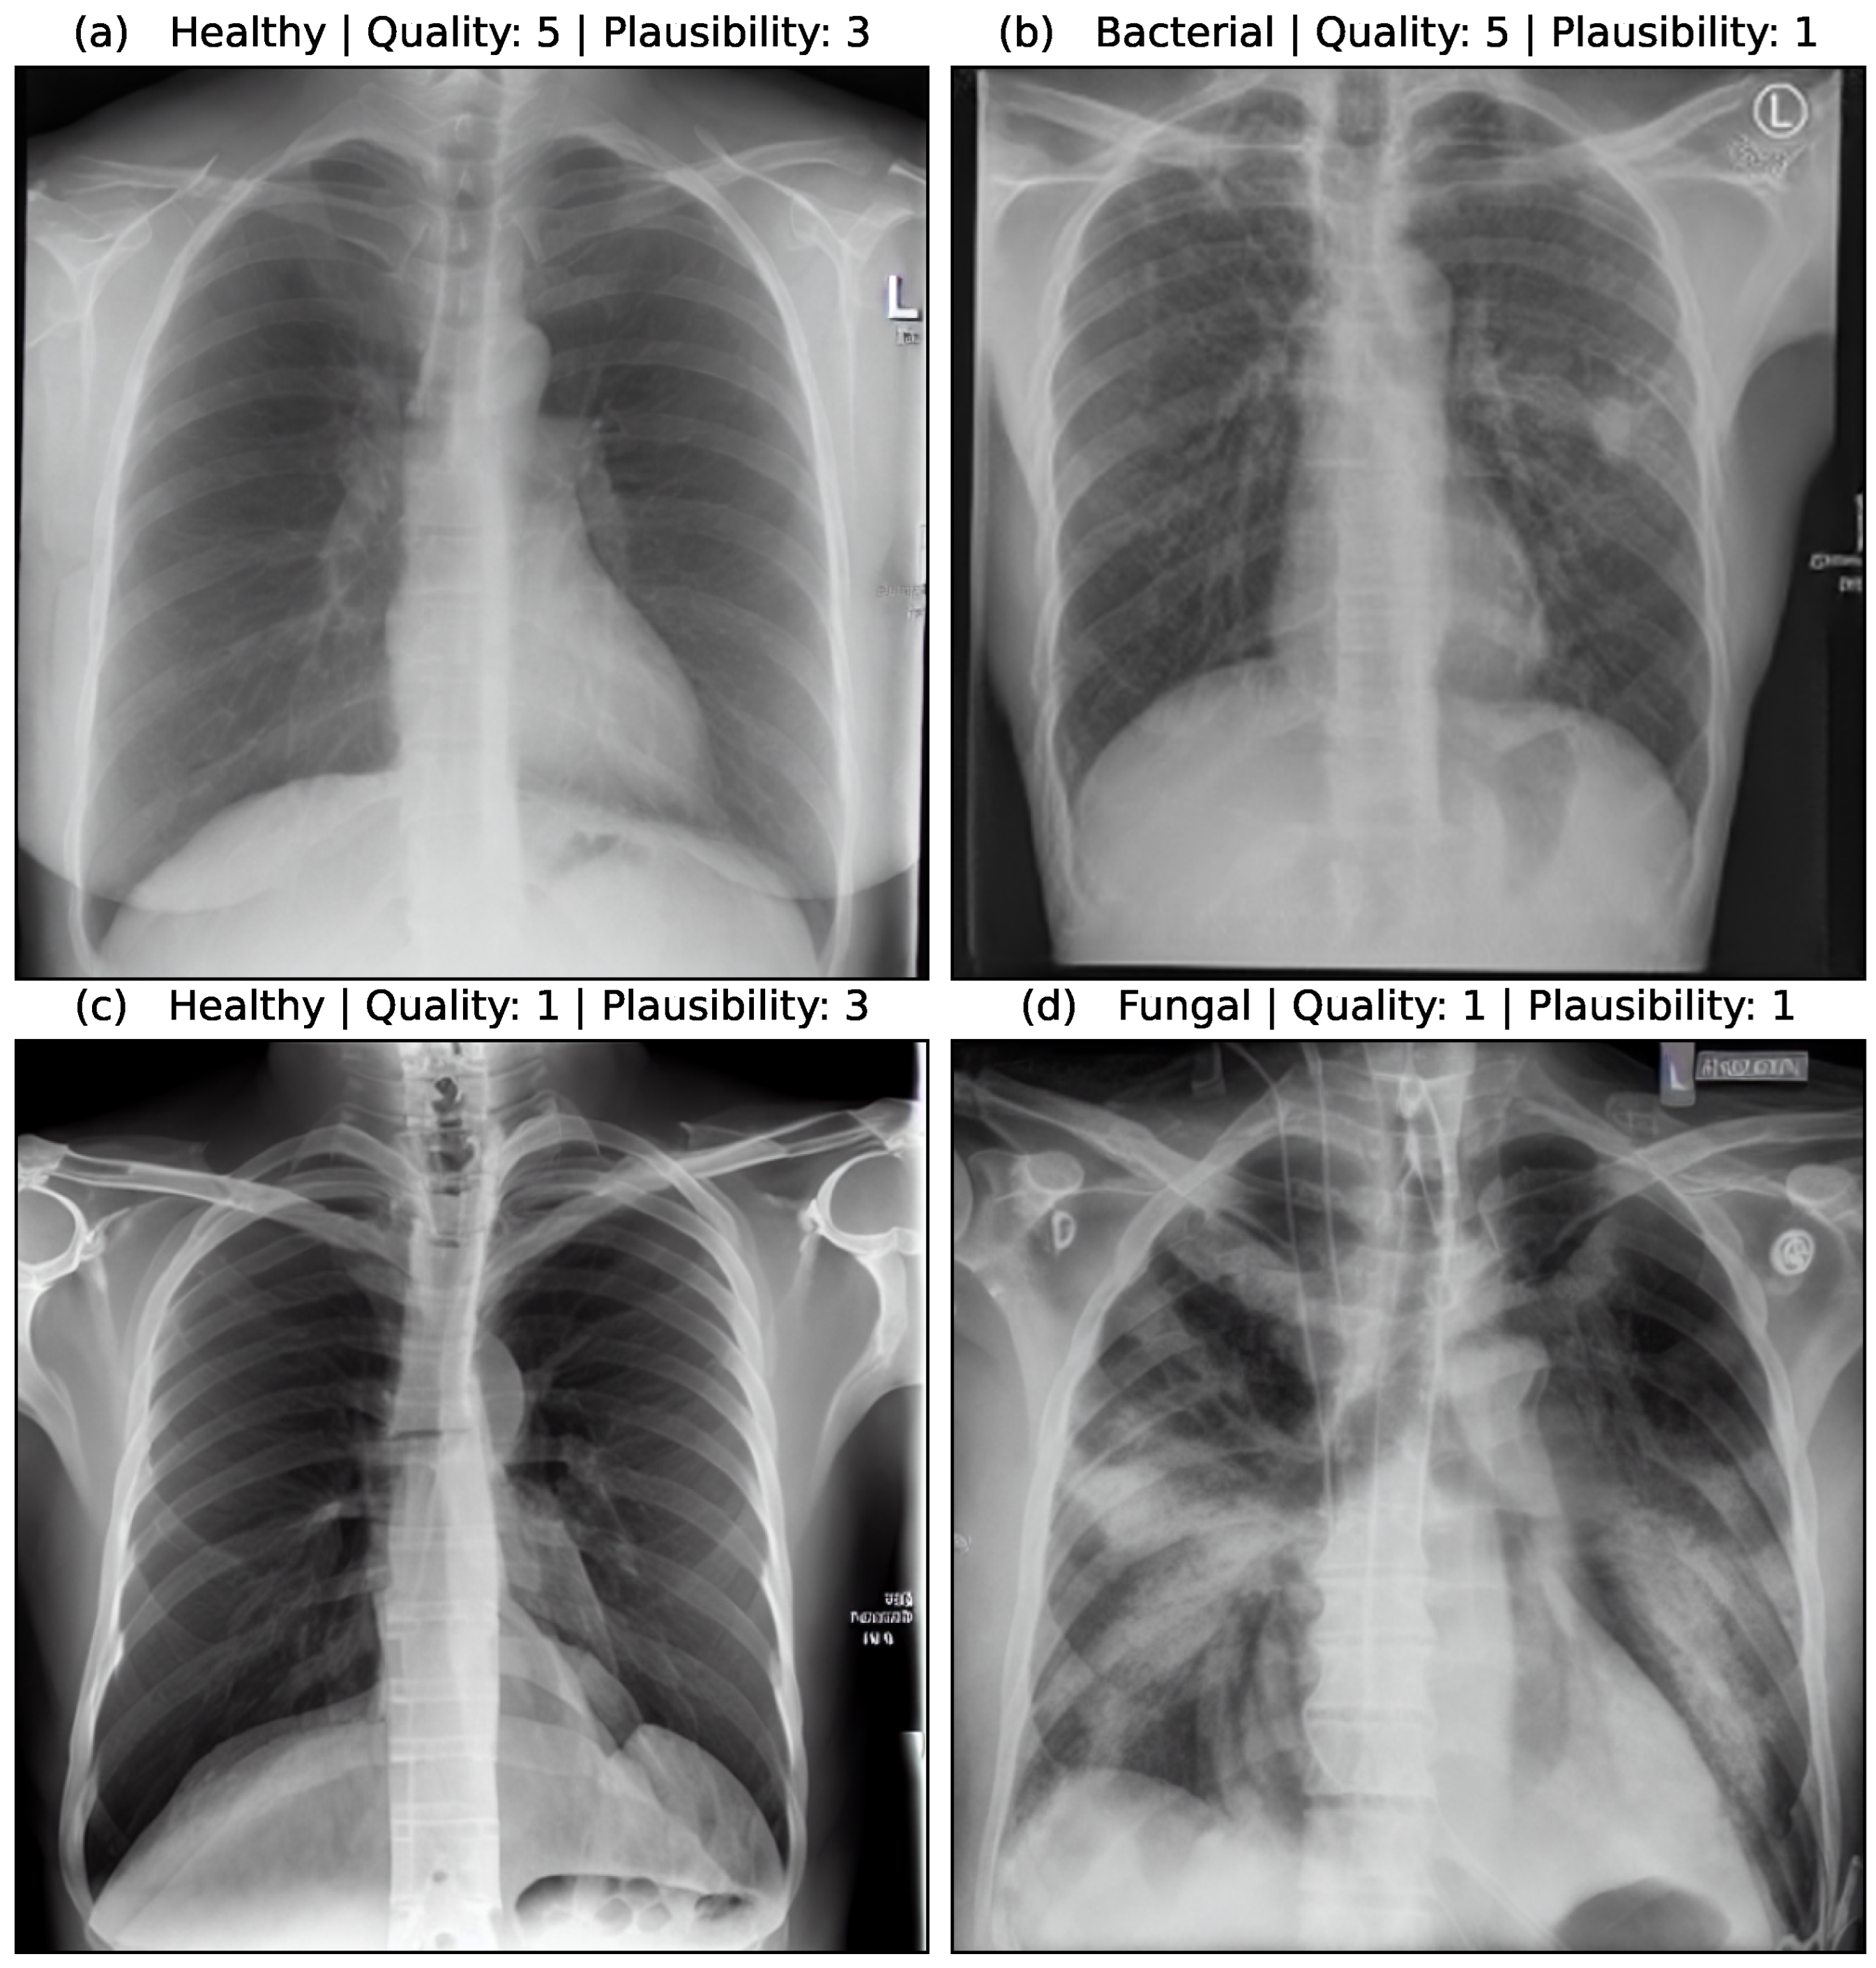

The quality of an image was assessed on a scale of 1 (lowest quality) to 5 (highest quality). Important aspects of the quality assessment are that thorax and lungs are shown as a whole, so that the anatomy is reproduced correctly and to scale. The sharpness and contours must be reproduced correctly. If a pathology was present, it was evaluated according to its characteristic appearance on a scale from 1 to 3 (1 = completely inappropriate, 2 = partly characteristic, 3 = characteristic). Important aspects of the plausibility assessment are to what extent the typical appearance of pneumonia is reproduced. This includes the density, the sharpness compared to the lungs, the relationship to other anatomical structures (heart, pleura) as well as the distribution pattern within both lungs (centrally emphasized, peripherally emphasized, division into the individual lung lobes).

Figure 5 shows the assessment of four synthetic image samples with high/low quality and high/low plausibility scores. In (a, b) the anatomical structures are reproduced realistically and the proportions are accurate. The pleura, diaphragm, heart contour and hilar vessels are reproduced with absolute precision. The breast shadow is also reproduced exactly in (a), which simulates a woman as the gender of the patient. The quality rating is accordingly rated score 5 without any gradations. The healthy state in image (a) is shown regularly with a quality score of 5. The bacterial pneumonia in (b) is rather atypical, a suspect bronchial carcinoma from the simulated image is more realistic. It does not reflect peripheral inflammation in the sense of bronchopneumonia or lobar pneumonia, hence the assessment of plausibility as inappropriate (score 1). Image (c) appears artificial in appearance, the diaphragm contours, the heart silhouette and the bones are not realistically reproduced, the image quality is only rated with score 1. In contrast, no pathology of the lung parenchyma is recognizable, but this is still realistic and therefore rated as score 3 in terms of plausibility. Image (d) also appears artificial in appearance, in particular the hints of foreign material/lines and heart contours are unrealistic (quality score 1). The inflammations of the lungs described also seem unrealistic for any type of pneumonia; a fungal infection is unrealistically shown (plausibility score 1).

Figure 5. Medical assessment of quality and plausibility for 4 synthetic image samples. (a) Healthy case with high quality and plausibility. (b) Bacterial case with high quality but low plausibility. (c) Healthy case with low quality but high plausibility. (d) Fungal case with low quality and plausibility.